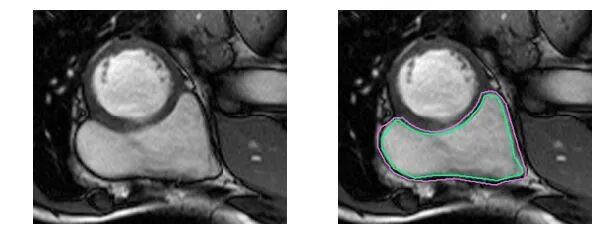

下面用几组图片来感受一下这种分割问题的困难。下图是右心室的MRI图片:

再困难一点:

而对于未训练过的肉眼,右心室区域是这样的:

基于FCN网络结构实现左、右心室分割:

Phi V. T.. A Fully Convolutional Neural Network for Cardiac Segmentation in Short-Axis MRI[C]. CVPR 2016.